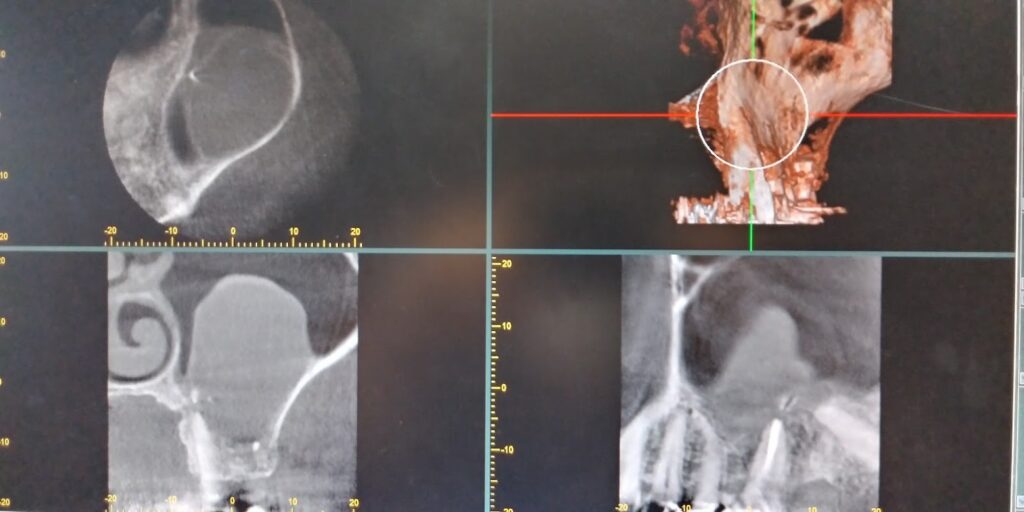

左側上顎洞内にうずら卵大の不透過像をみとめます。左側6は根管充填が実施されています。

左側6の根尖から連続して上顎洞粘膜が挙上されています。上顎洞病変の内部に根管治療材の一部迷入しています。今後残留していると病変に影響を与える可能性も否定できませんでし、病変の増大悪化考えられました。

左側上顎6の歯根は経上顎洞的に頬側根 口蓋根を切除しました。上顎洞内の嚢胞と嚢胞内の歯科材料異物は摘出されています。(術中CT)